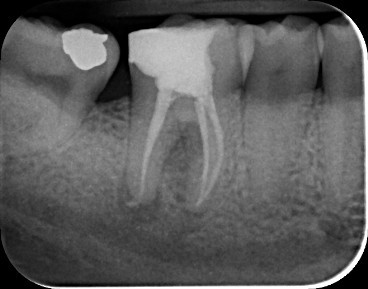

Case 2: Root canal treatment LR6